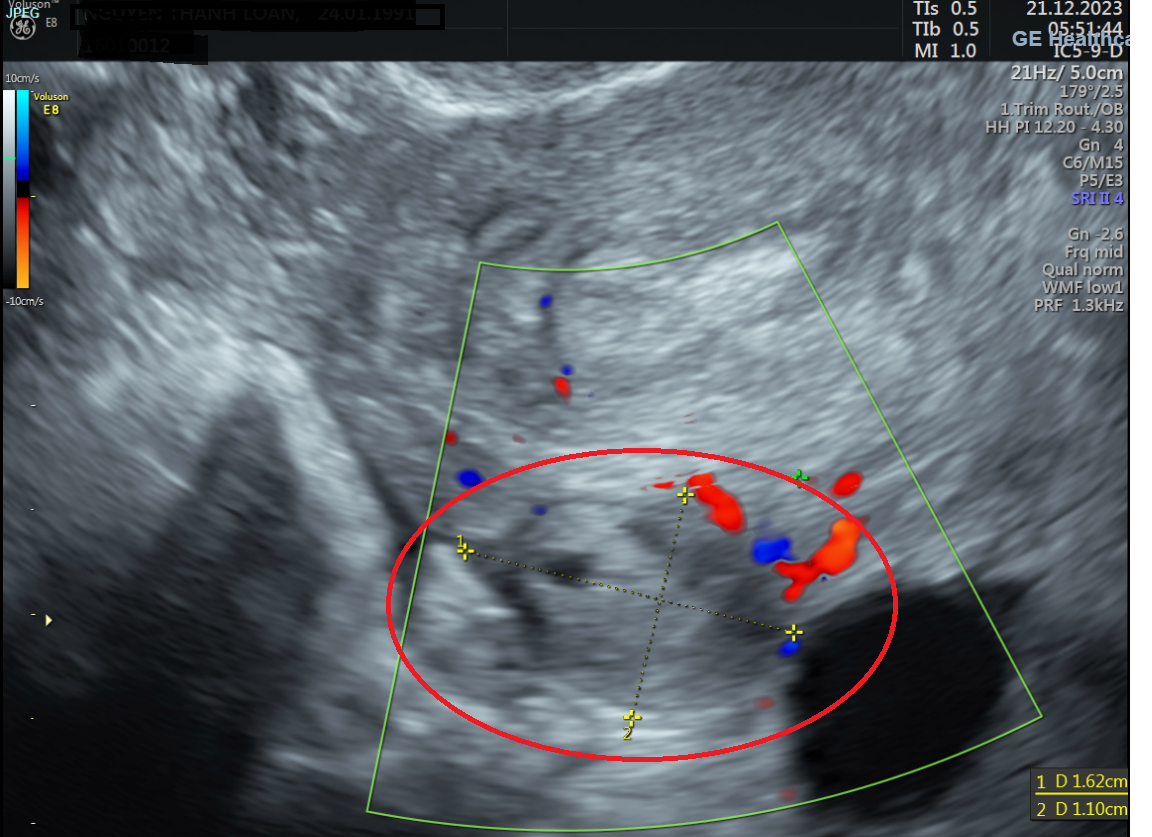

BSCKII Đỗ Văn Tú (Trưởng khoa Sản Phụ khoa - Bệnh viện Đa khoa Hồng Ngọc Yên Ninh) cho biết: “Khi siêu âm, chúng tôi không thấy hình ảnh phôi thai trong buồng tử cung dù trước đó chị L tự thử thai cho kết quả 2 vạch nhưng các bác sĩ lại thấy tại buồng trứng trái của bệnh nhân có khối kích thước 10x13cm, nghi ngờ thai ngoài tử cung, có khả năng phải phẫu thuật bỏ thai, tránh nguy hiểm đến tính mạng của mẹ.”

| Hình ảnh siêu âm cho thấy tại buồng trứng trái có khối KT: 11x15mm nghi ngờ thai ngoài tử cung |